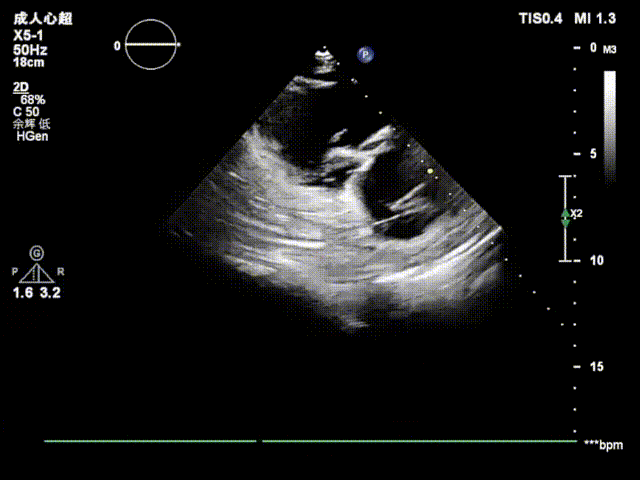

复查超声及造影提示封堵器位置形态稳定,无残余分流,手术圆满成功!

完全释放封堵器

术后超声